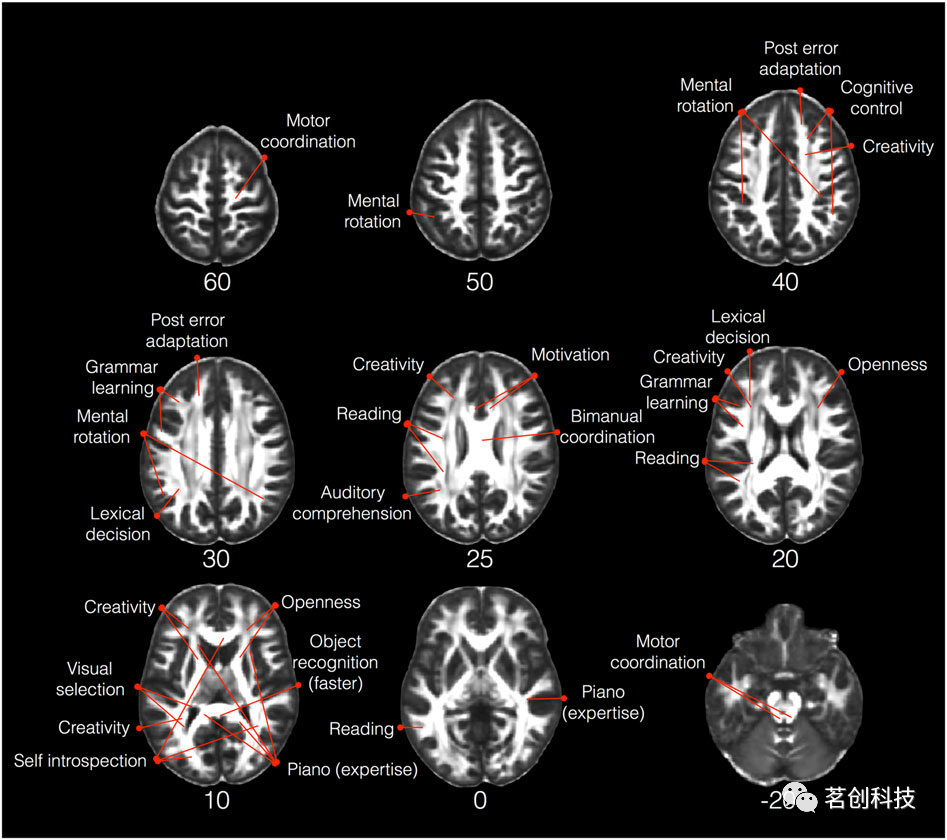

关于对行为的影响,有研究表明,在特定任务中行为表现的个体差异与任务相关通路的白质微观结构变化相关,即使在年轻健康人群中也是如此。例如,如图5所示,双手协调技能的变化与胼胝体中FA的变化相关,胼胝体是一个白质区域,包含初级运动区和辅助运动区之间的经胼胝体通路。在许多感觉、运动和认知领域也发现了类似的效应,包括视觉、听觉、运动技能和语言、读写能力、情感和动机、视觉空间、记忆和执行功能,以及创造力、音乐技能和个性等个人特征。

图5.在特定任务中行为表现的个体差异与白质微观结构的变化之间的相关性。